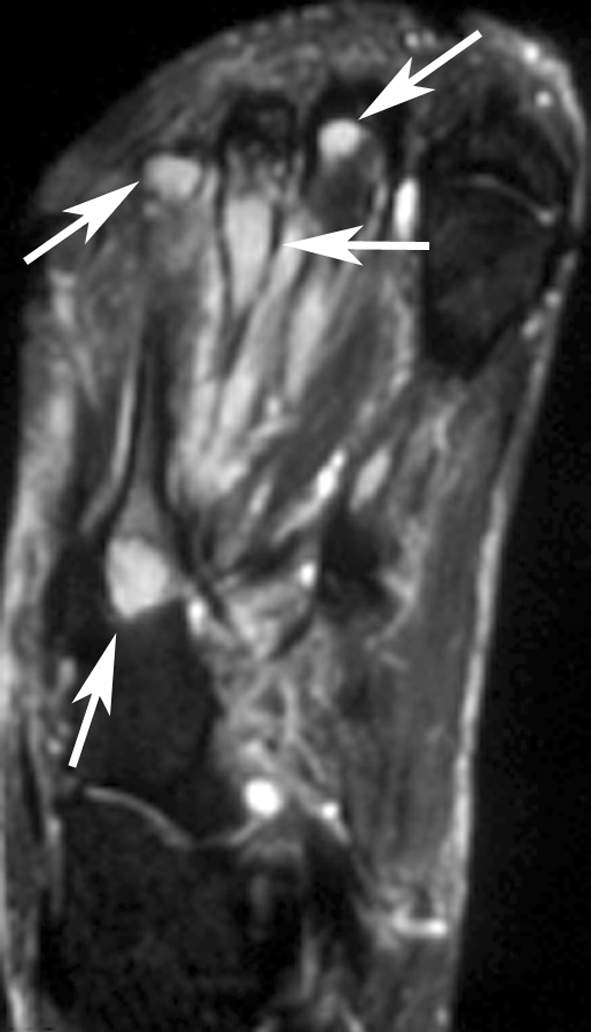

Radiologic images were available for 10 patients and were reviewed by an expert musculoskeletal tumor radiologist (DMP). The first metatarsal bone was involved in two patients (Fig. 2), and one patient each had involvement of the anterior ninth rib (Fig. 3), clavicle, T2 and T3 vertebrae, and multiple bones in a foot (Fig. 4). In the four patients with EH of soft tissue with available radiology, the lesion was located in the triceps muscle in two (Fig. 5) and one each had involvement of the flexor tendons of a hand and an index finger (Table 2).

Fig. 5A–C.

(A) The radiograph shows a tiny permeative, lytic focus in the posterior cortex of the midhumeral shaft (arrow). No calcifications are evident in nearby soft tissues. (B) An axial proton density MR image shows heterogeneous tumor deposits in the triceps muscle and an intracortical tumor deposit (arrow). (C) A sagittal proton density MR image shows multinodular tumor deposits with low-signal intensity inner rings (arrows), possibly related to hemosiderin deposition.

On radiographs the bone lesions often appeared lytic, septated, and expansile. (Fig. 2A; Table 2) The mean size of the bone lesions was 3.7 cm (range, 1.7-6 cm). One lesion showed a smooth, thick periosteal reaction. CT showed well-defined, septated, lytic lesions with cortical destruction and bony expansion (Figs. 2B, 3B). The lesions were well defined by MRI, being hypointense or isointense to muscle on T1-weighted images, and hyperintense on T2-weighted images (Fig. 4). In one patient, a small nodule of tumor extended through a region of destroyed cortex into adjacent soft tissues. Preoperative embolization images available for one patient showed an intense blush in the tumor. The mean size of the soft tissue lesions was 5.7 cm (range, 2–12 cm). Radiographs showed a small, lytic intracortical focus in the humerus of one patient (Fig. 5A) and erosion of a phalanx in another; no lesion was evident in the third. MRI showed the mass to be well defined with an unusual pattern of low-signal inner rings on proton density, T2-weighted, and gradient echo images in three of three patients (Fig. 5C). A satellite lesion was observed in one patient and a small intracortical deposit in another (Fig. 5B).